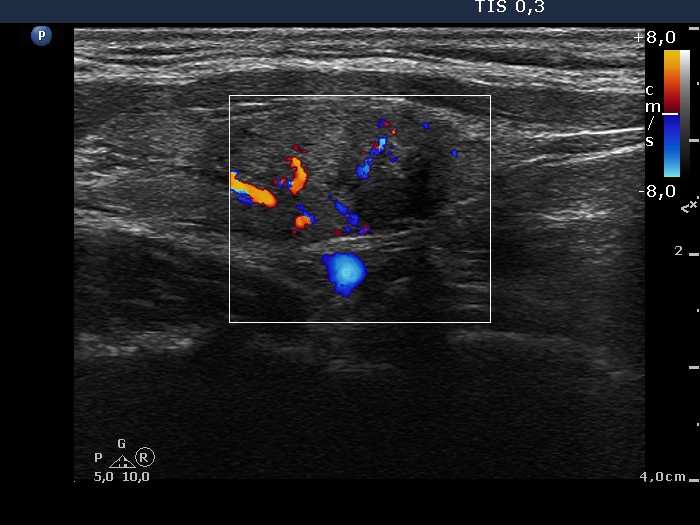

Consecutively operated patients with autoimmune thyroid disease - case 56 (conp 039) (ultrasonographic picture 7)

Left lobe, longitudinal scan, color Doppler mode. The nodule presents intranodular blood flow.